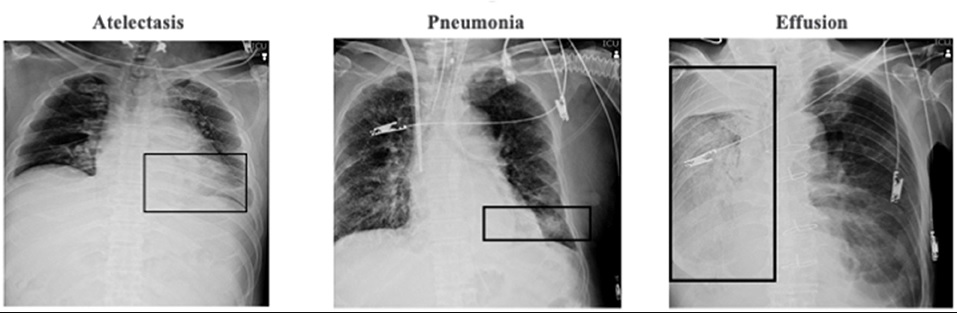

Superiority of Supervised Machine Learning on Reading Chest X-Rays in Intensive Care Units.Frontiers in Medicine :2021.676277

機械学習(machine learning technique)を使って胸部X線写真の異常を臨床医より速く正確に見出すことができるか研究しています.千葉大学の集中治療室で撮影されたポータブル胸部X線写真380枚と米国国立衛生研究所で保管された1720枚の2つのデータを訓練データ(training data)と強化データ(study data)に分けて解析しています.各々の画像は「無気肺」「胸水」「肺炎」「異常なし」の4つにラベリングされていて,機械学習モデルはDenseNet-121を用いて,アンサンブル学習によってアルゴリズムを強化しました.その後テストデータを用いてこの機械学習の診断能および集中治療臨床医との速度比較を行いました.その結果,診断能のAUCは学習によって向上し全ての種類において0.9以上となり,臨床医に比べて70倍の速さで診断することができました(9.66秒対12分).今後,この手法を用いて日々の胸部X線写真の異常を自動で同定し,より患者さんにとって有益な情報提供と医療資源の効率化を目指したいと考えています.

NIHリポジトリのテスト画像サンプル

ROC解析はサンプルサイズ25、50、75、100%で実施した。

(A)無気肺に対するROC解析。

(B)胸水に対するもの。

(C)肺炎に対するもの。

(D)緊急事態なし。